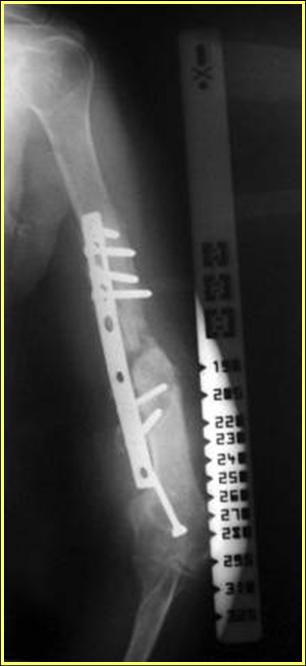

На примере два случая, извиняюсь за качество снимков, снимки и случаи из бывшего союза.

Первая больная с "успехом" была прооперирована 6 раз различными методами открытого и закрытого

остеосинтеза, включая то, что в Кисловодске заезжим австралийским "кудесником" на ложный сустав уложена скорлупа от страусиновых яиц. Последняя операция одиноким локинг плейт в одной из клиник.

Через год по поводу тех же проблем сделали ревизию, оригинальную пластину оставили как есть, только укрепили добавлением еще одной пластины и сделали костную пластику.

Через два месяца увидели признаки консолидации.

Второй случай, также после множественных операций: